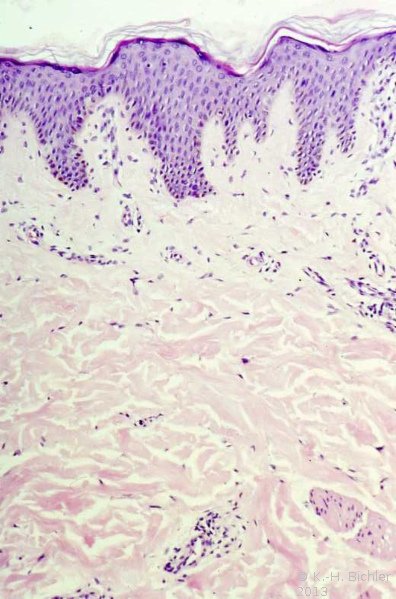

- Abbildung HG1:

- Lichen sclerosus et atrophicans

- Hyperkeratose

- Hydrophische Degeneration

- Ödem, Kollagenhomogenisierung

- Entzündliche Infiltrate

Histologisch findet sich beim Lichen sclerosus et atrophicans eine atrophische Epidermis, Sklerosierung und Ödem (Abbildung HG1).